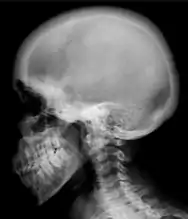

Ground glass density of the skull.[17]